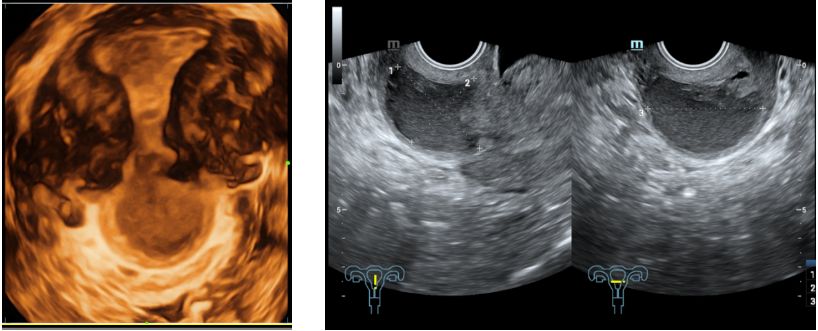

2019-12-30本院经阴道三维子宫附件超声检查示:子宫后位,正常大,内膜厚0.9cm(双层)。前峡部见4.0*3.1cm液性暗区,与宫腔相通,内液稠,宫腔内见多个偏强回声,较大约位于下段1.0*0.9*0.3cm,内见血流。余宫壁回声均匀。双卵巢正常大,回声无殊。右卵巢内见1.8*1.3*2.0cm囊性回声,内液稠。诊断结果:子宫正常大,前峡部暗区(合并内异病灶待排),宫腔多发偏强回声(息肉考虑),右卵巢内囊性块(内异囊肿考虑)。

子宫瘢痕憩室的诊断主要依靠影像学方法,包括:经阴道三维超声、MRI、子宫输卵管造影/宫腔声学造影、宫腔镜检查。宫腔镜检查是诊断子宫瘢痕憩室的金标准,但有创、费用高。经阴道三维超声由于安全无创、经济方便、可重复,是临床上子宫瘢痕憩室的一线诊断手段。

关于子宫瘢痕憩室患者行经阴道三维超声检查时的检查参数,如残余肌层厚度(residual myometrium thickness, RMT)、憩室凹陷深度(depth, D)、憩室长度(length,L)、憩室宽度(width,W)等,与患者月经异常症状、以及手术有效性的相关性是一个尚未明确且值得研究探讨的问题。最近发表的一项单中心的针对241例子宫瘢痕憩室患者的回顾性研究发现,憩室越深、越长、越宽,经期时间越长;经期大于等于15天组较小于15天组,其RMT/D和RMT/(RMT+D)显著变小;其中,憩室长度(L)是所有超声指标中与经期延长最正相关的指标,但其与手术有效性无关;RMT/D和RMT/(RMT+D)被发现与手术有效性相关(其中RMT/(RMT+D)的临界值为0.496,灵敏度为53.0%,特异性为61.4%),即残余肌层厚度越厚、憩室凹陷深度越浅,手术治愈可能性越高。此外,有研究发现D/RMT与下次妊娠发生瘢痕裂开具有显著相关性,且当D/RMT大于1.3035时,下次妊娠发生瘢痕裂开的风险大于50%;该预测方法的灵敏度达到71%,特异性达到94%。这些研究可能对于临床症状评估咨询、是否进行手术的抉择(挑选出能经手术获益的患者)起到一定指导作用。